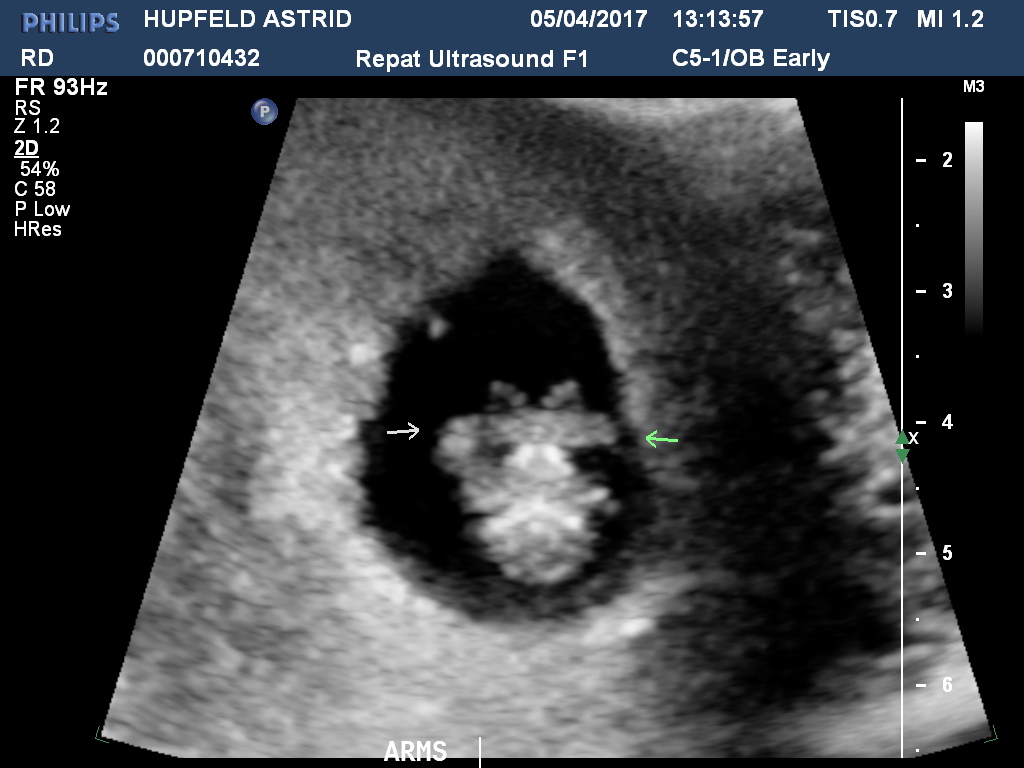

HUPFELDASTRID20170405131357176 Previous Next Published June 28, 2017 at 1024 × 768 in First Trimester.